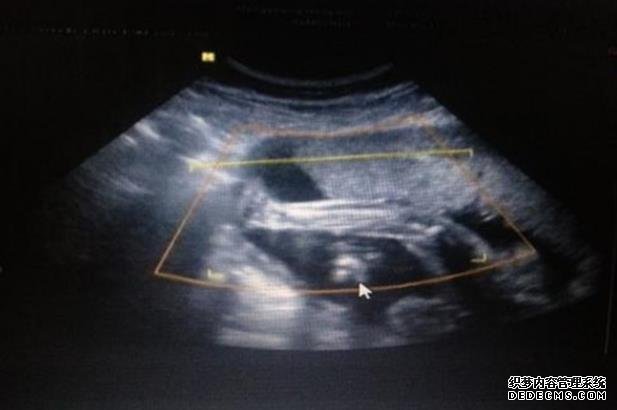

石家庄代孕手术费用 石家庄私人试管医院,做试管没做好这些准备可不行! ‘3个月彩超怎么看男孩女孩三个月的彩超’